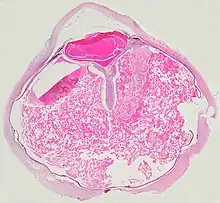

A case of Coats' disease, showing total retinal detachment with subretinal exudate containing cholesterol crystals and a fibrous nodule in the posterior pole

Grossly, retinal detachment and yellowish subretinal exudate containing cholesterol crystals are commonly seen.

A case of Coats' disease, showing total exudative retinal detachment, and subretinal exudate containing cholesterol crystals (H&E)

Microscopically, the wall of retinal vessels may be thickened in some cases, while in other cases the wall may be thinned with irregular dilatation of the lumen.[10] The subretinal exudate consists of cholesterol crystals, macrophages laden with cholesterol and pigment, erythrocytes, and hemosiderin.[11] A granulomatous reaction, induced by the exudate, may be seen with the retina.[12] Portions of the retina may develop gliosis as a response to injury.